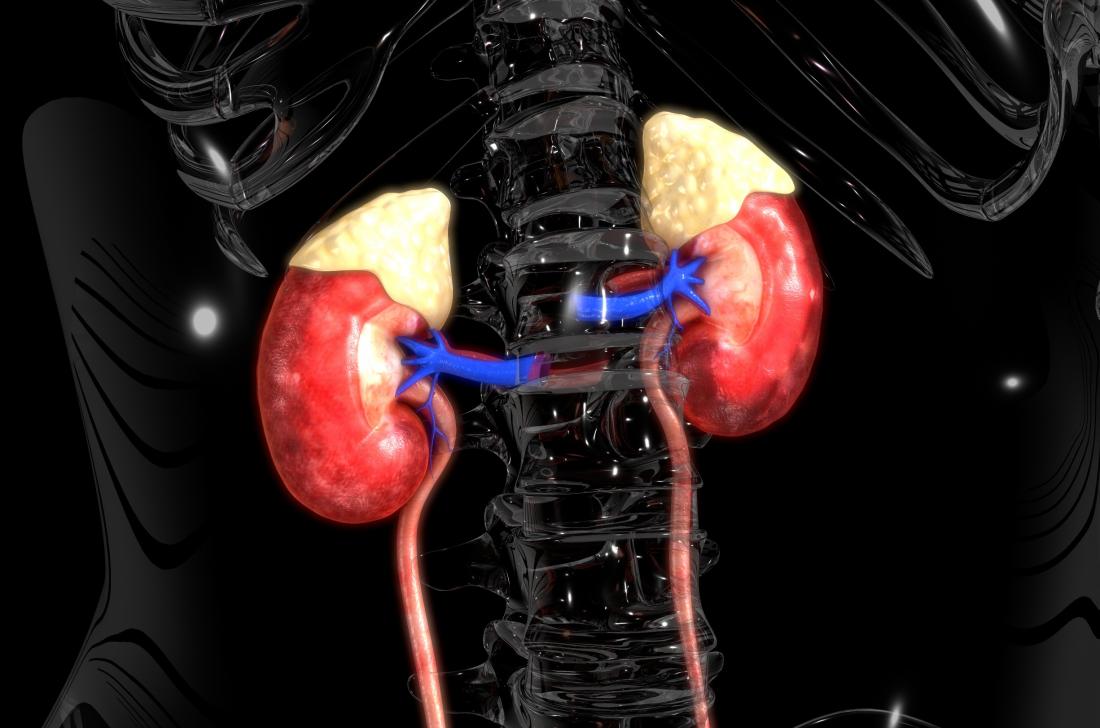

کلیه ها به طور طبیعی سطح فسفات را کنترل می کنند. اما اگر کلیه ها به درستی عمل نکنند، نمی توانند فسفات اضافی را از بین ببرند و این امر منجر به افزایش فسفات در بدن می شود.

استخوان ها برای بازسازی، رشد و مقاومت نیاز به مواد معدنی و هورمون ها دارند. کلیه ها مقدار فسفر و کلسیم را در خون متعادل می کنند. اگر این مواد خارج از تعادل باشند، باعث خروج کلسیم از استخوان و تضعیف آن ها می شوند.

از آنجایی که کلیه ها تعادل مواد معدنی و سایر مواد شیمیایی را کنترل می کنند، بیماری مزمن کلیه می تواند باعث ایجاد بیماری های معدنی و استخوانی شود. کسانی که نارسایی کلیه دارند و دیالیز می شوند بیشتر در معرض خطر هستند.